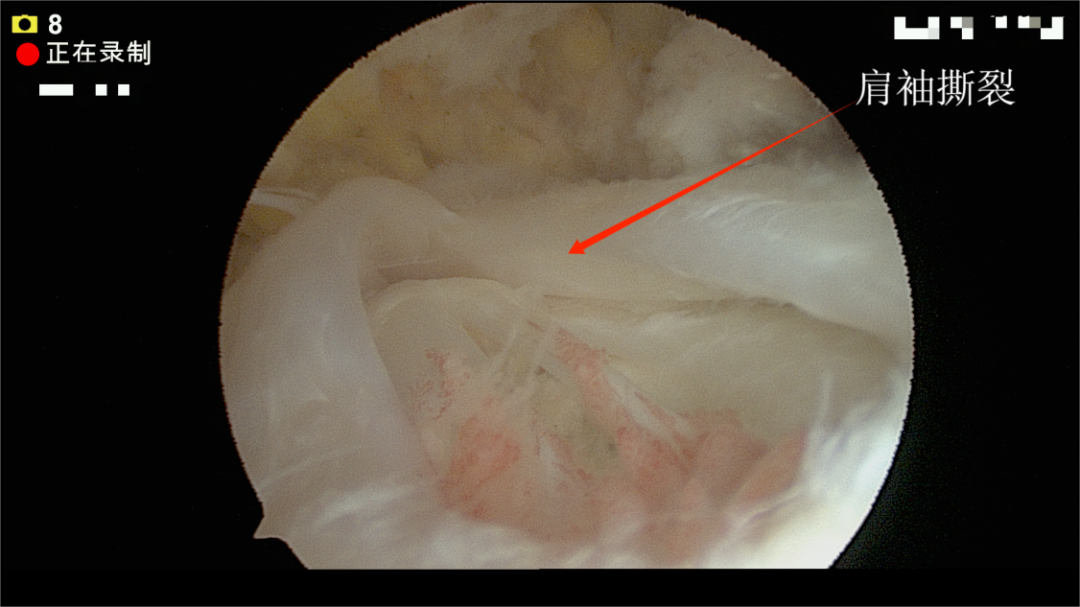

关节镜下:肩袖撕裂状态

家住防城区的韦女士(化姓),她某次抬手晾衣服后,肩膀就开始疼痛、越来越没力气,自己活动时还常有响声。她一直以为是“肩周炎”,便自行贴膏药进行治疗,并加以锻炼,但均未见好转,深受其扰。便来到我院筋伤门诊,经过门诊医师详细查体和磁共振检查,发现真正的元凶是——肩袖损伤。肩袖是肩关节周围一组重要的肌腱,像四根绳索一样稳定着肩膀。她的“绳索”因长期劳损和退变出现了撕裂。